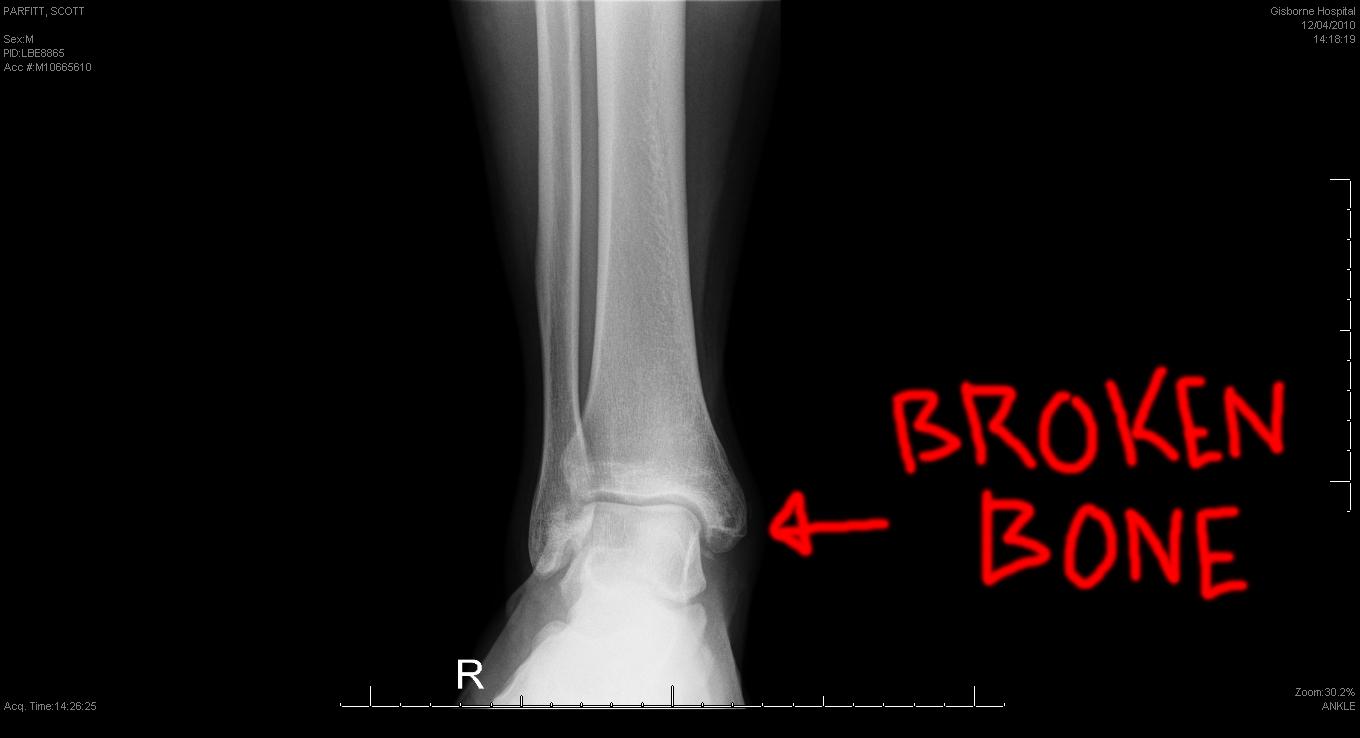

Gli esiti di fratture articolari che hanno coinvolto il malleolo tibiale o peroneale, fratture dell’estremo distale di tibia oppure un quadro di degenerazione cartilaginea possono portare alla formazione di calcificazioni articolari, corpi mobili oppure “osteofiti” che deformano l’articolazione rendendola non più congruente e quindi con un arco di movimento ridotto.

Gli accertamenti strumentali sono essenzialmente rappresentati da una radiografia standard in due proiezioni della caviglia, sufficiente a dimostrare la deformazione dei capi articolari, eventualmente accompagnata da una RM per meglio definire la situazione dei tessuti molli (capsula articolare, legamenti, cartilagine, etc.)